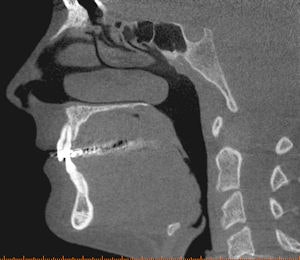

![]() |

| Cone-beam CT images from two different patients. The top CT image was taken to evaluate the mandible for implant purposes; the other was taken to evaluate the maxilla for implant purposes. The images show how much more of the head was exposed than needed to be. Also, one CT was done at 0.25 voxels, which is more resolution than is needed for a typical implant CT. Images courtesy of Dr. Bernard Friedland. |